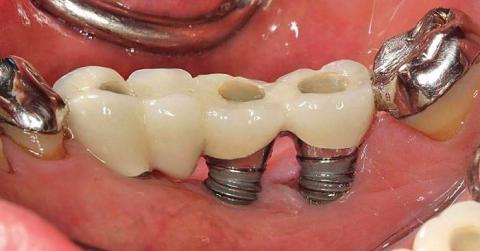

The infection, however, was anything but minor. It was a relentless enemy, a condition known as peri-implantitis. As the team at Mission Implant Center expertly explains, this is an inflammatory process that affects the soft and hard tissues around a dental implant. Unlike the gum around a natural tooth, the tissue around an implant is more susceptible to inflammation and has a poorer blood supply, allowing the infection to burrow deep.

In Aling Rosa's case, the infection was eating away at what little jawbone she had left. The implant, placed without adequate bone, was a ticking time bomb. The bone marrow, the very core of her jaw's strength, was now under siege.

They visited a reputable prosthodontist in Makati. The 3D scan revealed the devastating truth: severe bone loss around the failing implant. The infection was so advanced that the new implant had to be removed immediately, the area meticulously cleaned of infected tissue, and a complex bone graft procedure performed—all to salvage what was left of her jawbone before even thinking about a new tooth.